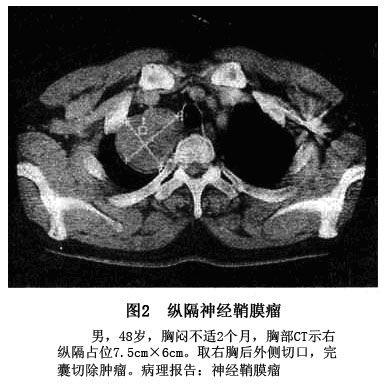

2.CT扫描显示 肿瘤位于后纵隔,多靠近椎旁,肿瘤边界清楚。呈圆形、卵圆形,良性或恶性肿瘤部分病例可以有分叶(图2)。